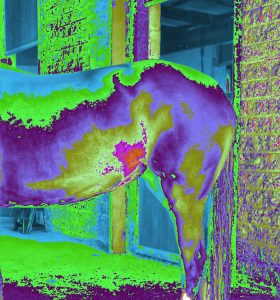

ERIC can detect injuries and sickness with horses.

Pictures show these horses have different body injuries and sickness.

Pictures show these horses have different body injuries and sickness.